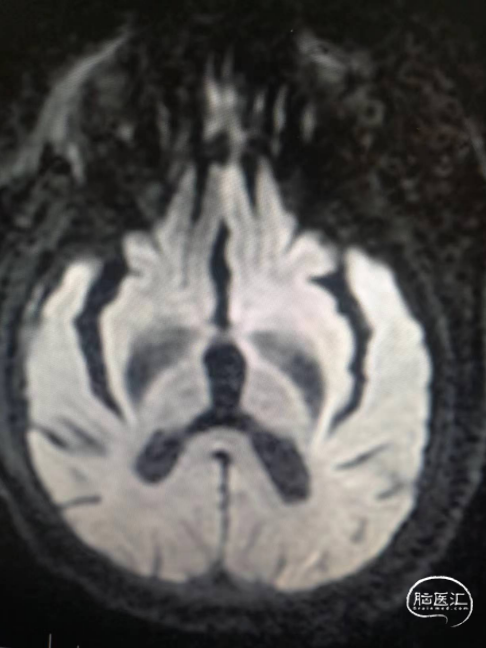

术前影像信息

符合脑内多发缺血变性灶、梗死灶(左侧大脑半球大面积急性梗死)、软化灶T2-FLAIR/DWI表现;

符合颅脑动脉硬化并多发狭窄MRA表现,左侧颈内动脉颅内段、大脑中动脉及分支未见显示,考虑闭塞或重度狭窄,建议CTA进一步检查。